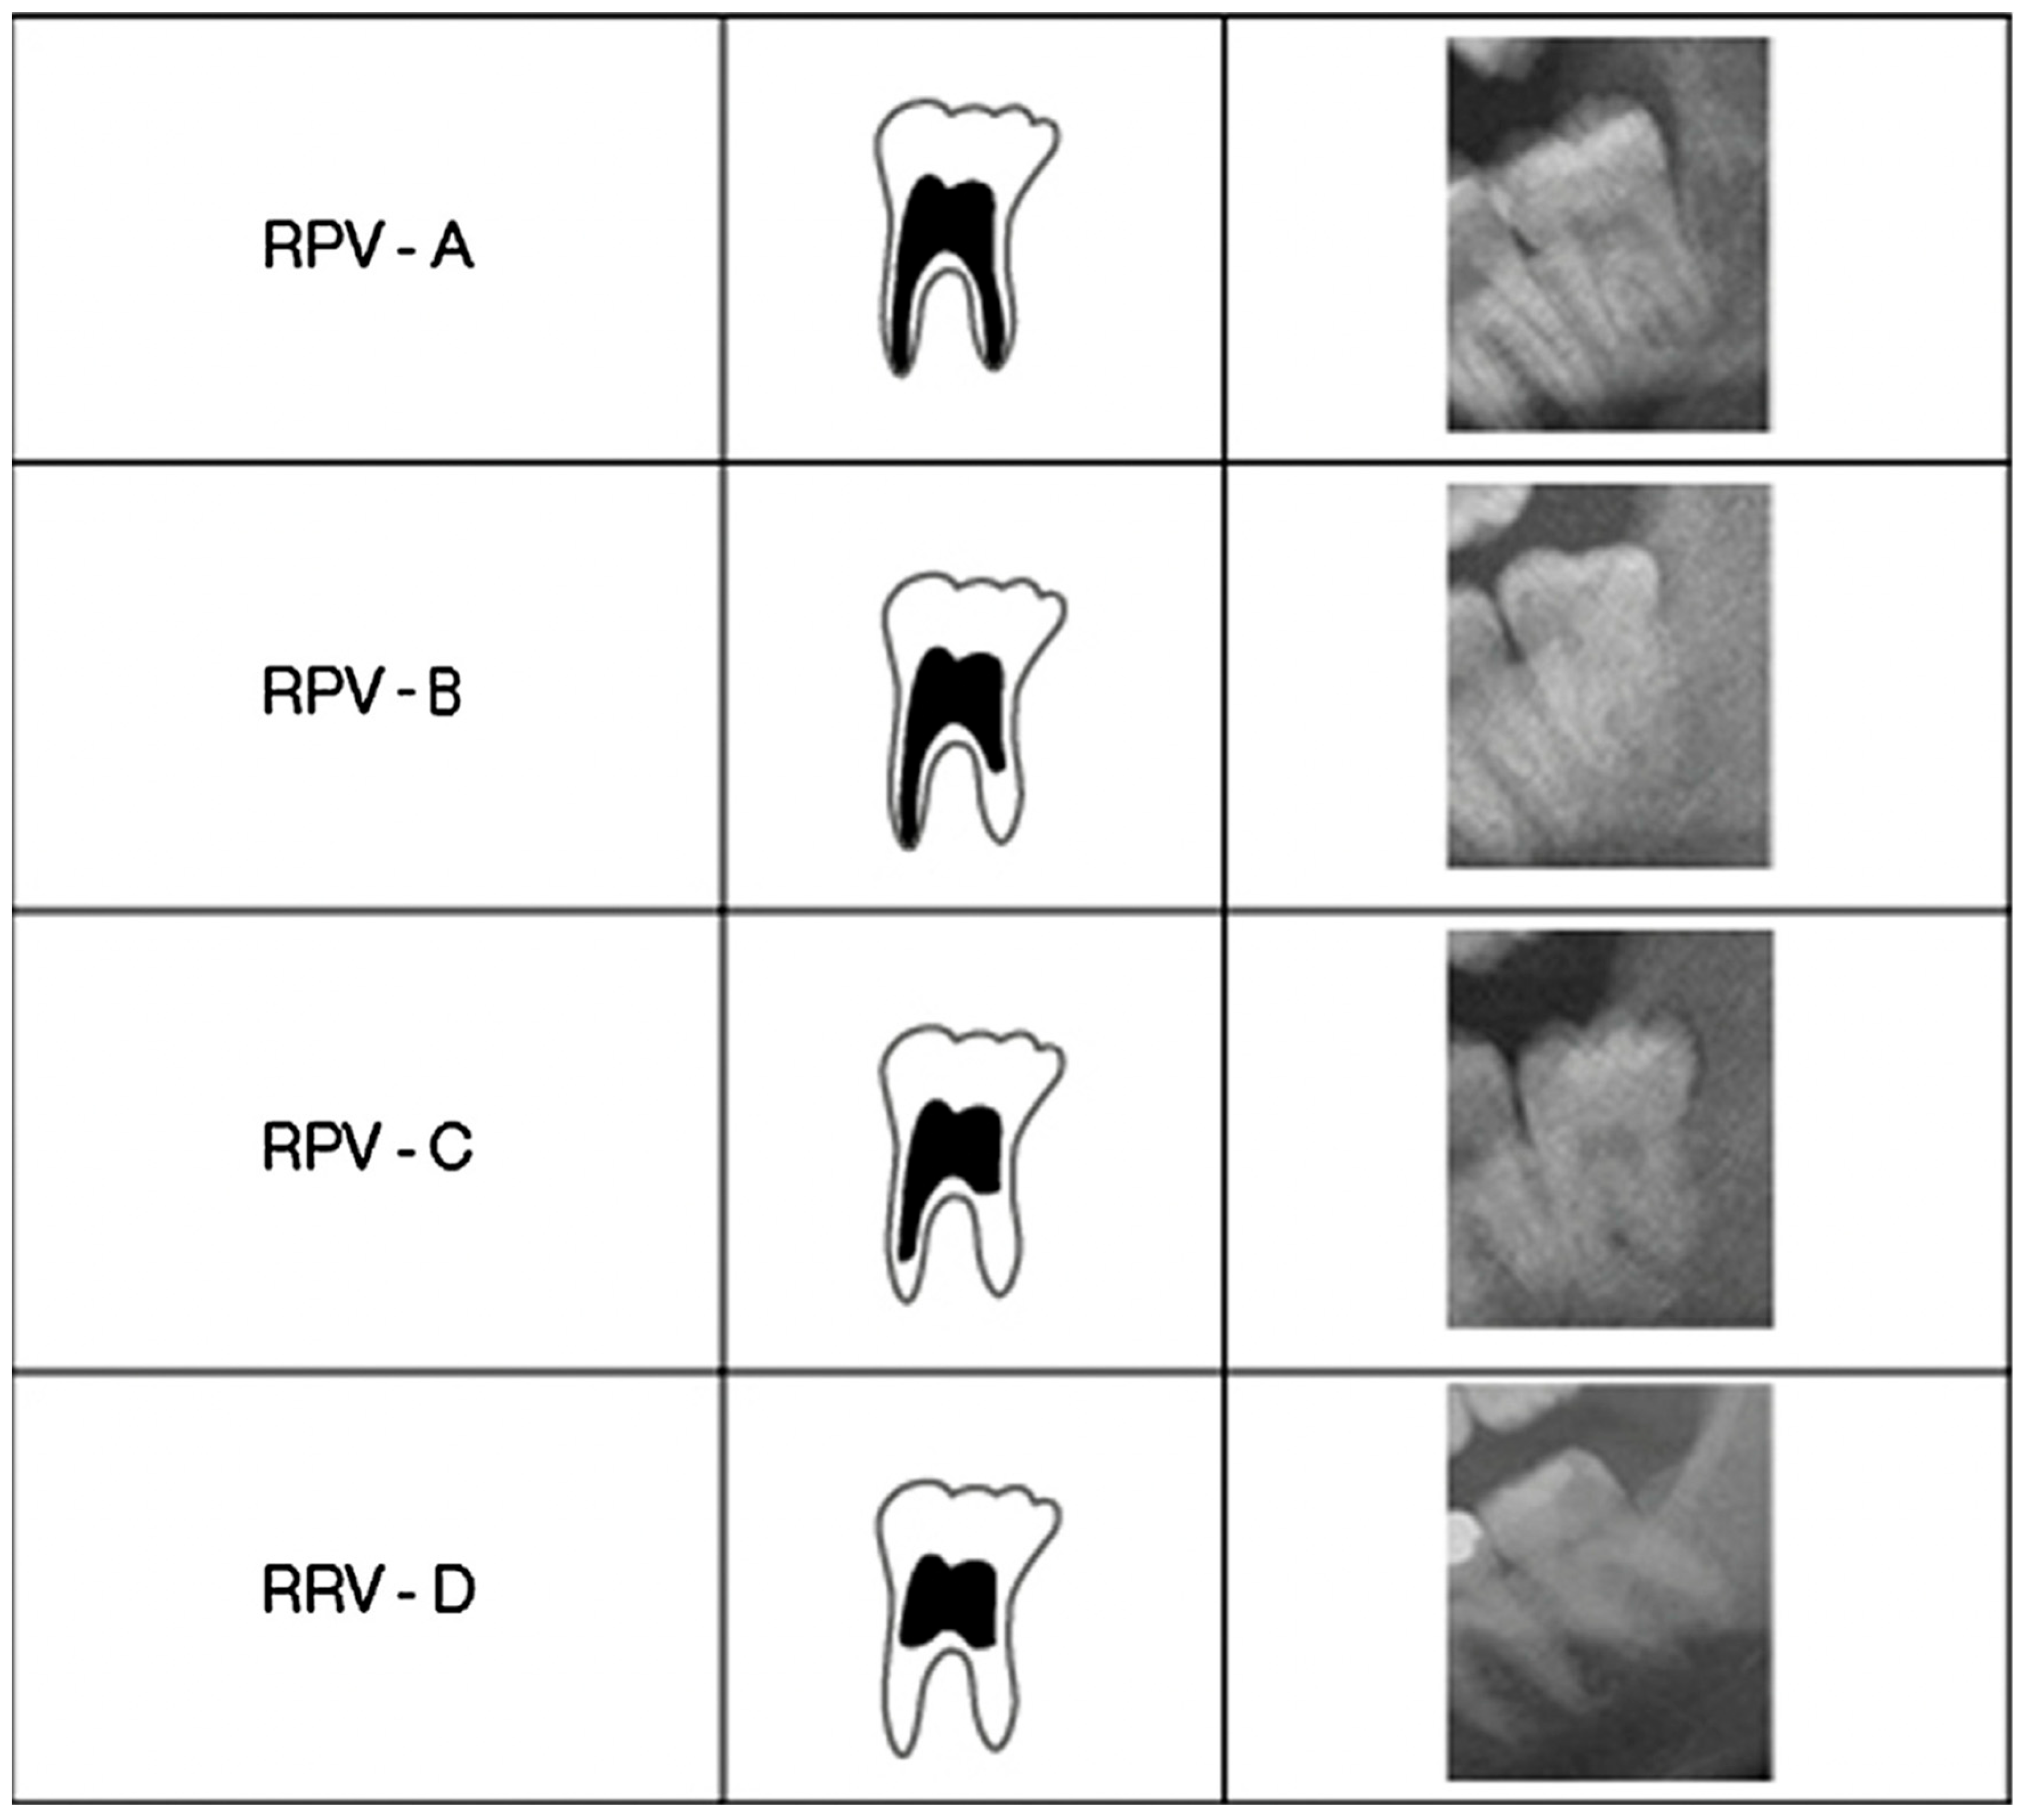

- Lucas, V.S.; McDonald, F.; Andiappan, M.; Roberts, G. Dental Age Estimation-Root Pulp Visibility (RPV) patterns: A reliable Mandibular Maturity Marker at the 18 year threshold. Forensic Sci. Int. 2017, 270, 98–102. [Google Scholar] [CrossRef] [PubMed]

- Olze, A.; Solheim, T.; Schulz, R.; Kupfer, M.; Schmeling, A. Evaluation of the radiographic visibility of the root pulp in the lower third molars for the purpose of forensic age estimation in living individuals. Int. J. Leg. Med. 2010, 124, 183–186. [Google Scholar] [CrossRef] [PubMed]

- Guo, Y.C.; Wang, Y.H.; Olze, A.; Schmidt, S.; Schulz, R.; Pfeiffer, H.; Chen, T.; Schmeling, A. Dental age estimation based on the radiographic visibility of the periodontal ligament in the lower third molars: Application of a new stage classification. Int. J. Leg. Med. 2020, 134, 369–374. [Google Scholar] [CrossRef] [PubMed]